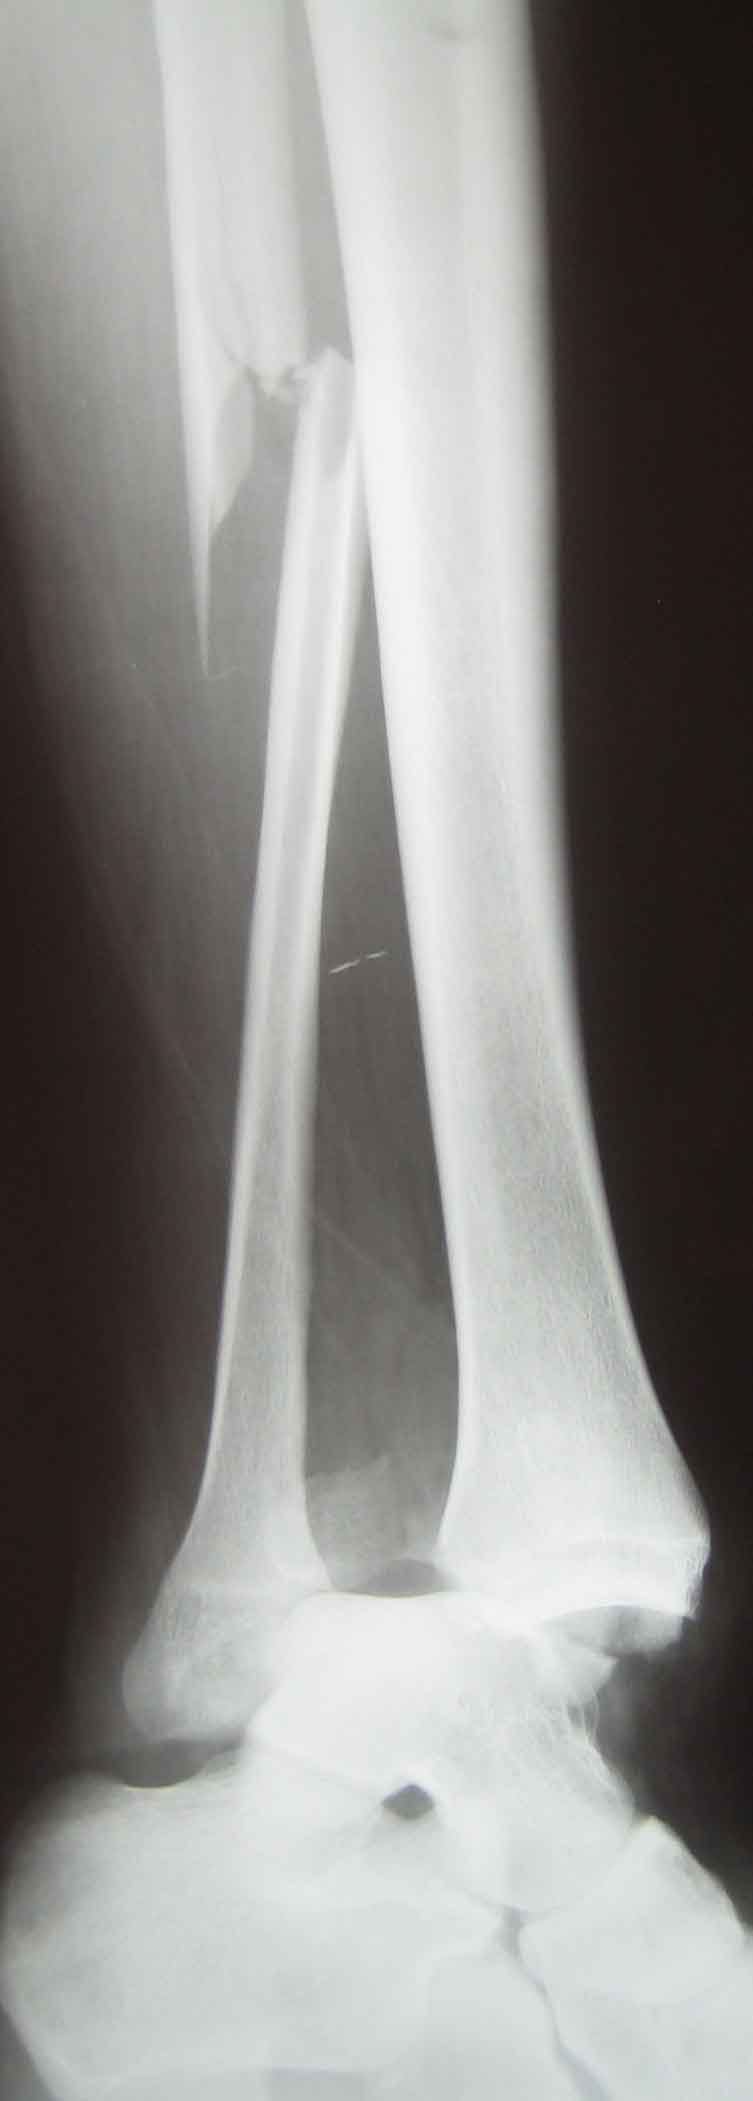

Д-з: закрытый переломо-вывих правого голеностопного сустава, перелом

внутренней лодыжки и заднего края большеберцовой кости, перелом

малоберцовой кости в средней трети, разрыв межберцового синдесмоза,

вывих стопы.